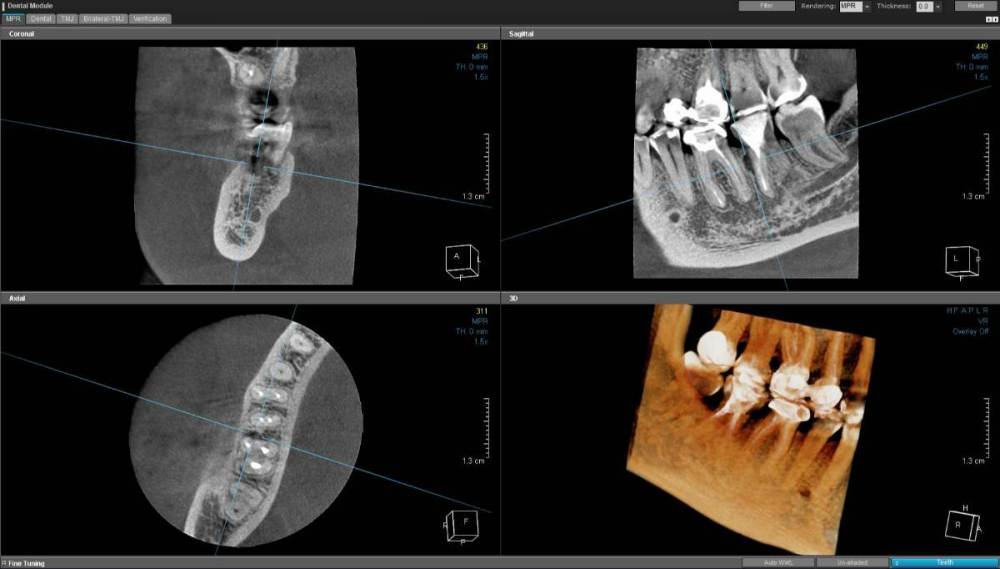

Еврейка Опубликовано 30 января, 2023 Поделиться Опубликовано 30 января, 2023 Добрый день. в апреле 2022 г установила коронку на зуб 46 перед этим прошла подготовку ( поставили штифт) . в июне 2022 г между 47 и 46 зубами на десне обнаружился свищ. все лето и осень выясняли откуда свищ, перелечили каналы на 47 зубе. свищ то исчезал то появлялся. В ноябре 2022 врач назначил пропить доксициклин . свищ исчез но я переболела гриппом в конце 2022 и он опять проявился. в январе 2023 г сделала КЛКТ https://disk.yandex.lv/d/ZXTOp24oEgl5Fg на нем мой врач увидела кариес на 47 зубе ( между 47 и 46 зубом ) , перелечили его , но через неделю опять напухла десна, вскрылся свищ и появилось гнойное отделяемое. сейчас врач предлагает сделать посев из свища и пропить антибиотики согласно посеву. насколько оправдана такая тактика ? если кто сможет посоветовать к кому можно обратиться в кемеровской, новосибирской областях за грамотной диагностиках - прошу написать мне Ссылка на комментарий

wladdX Опубликовано 1 февраля, 2023 Поделиться Опубликовано 1 февраля, 2023 В 8,5 Мб нет снимка(-ов). Собственно, он нужен для понимания динамики процесса (лучше, хуже или без изменений). По состоянию на 11.01.2023 имеется очаг разрежения костной ткани 2х4х6 мм вдоль передней поверхности переднего(медиального) корня и неявные признаки перфорации корня (очень неявные, полной уверенности нет). Нужно, чтоб КТ посмотрел эндодонтист (именно КТ полностью, скриншотов недостаточно). По моему мнению, необходимо удаление зуба 47. На истину в последней инстанции не претендую. 1 Ссылка на комментарий